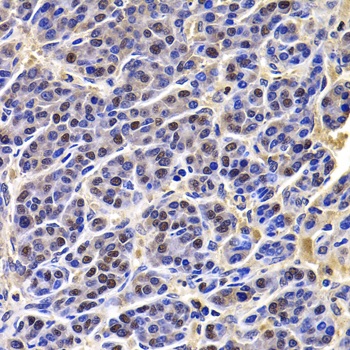

Immunohistochemistry - HIRIP3 Polyclonal Antibody

Immunohistochemistry of paraffin-embedded human liver cancer using HIRIP3 antibody at dilution of 1:100 (40x lens).